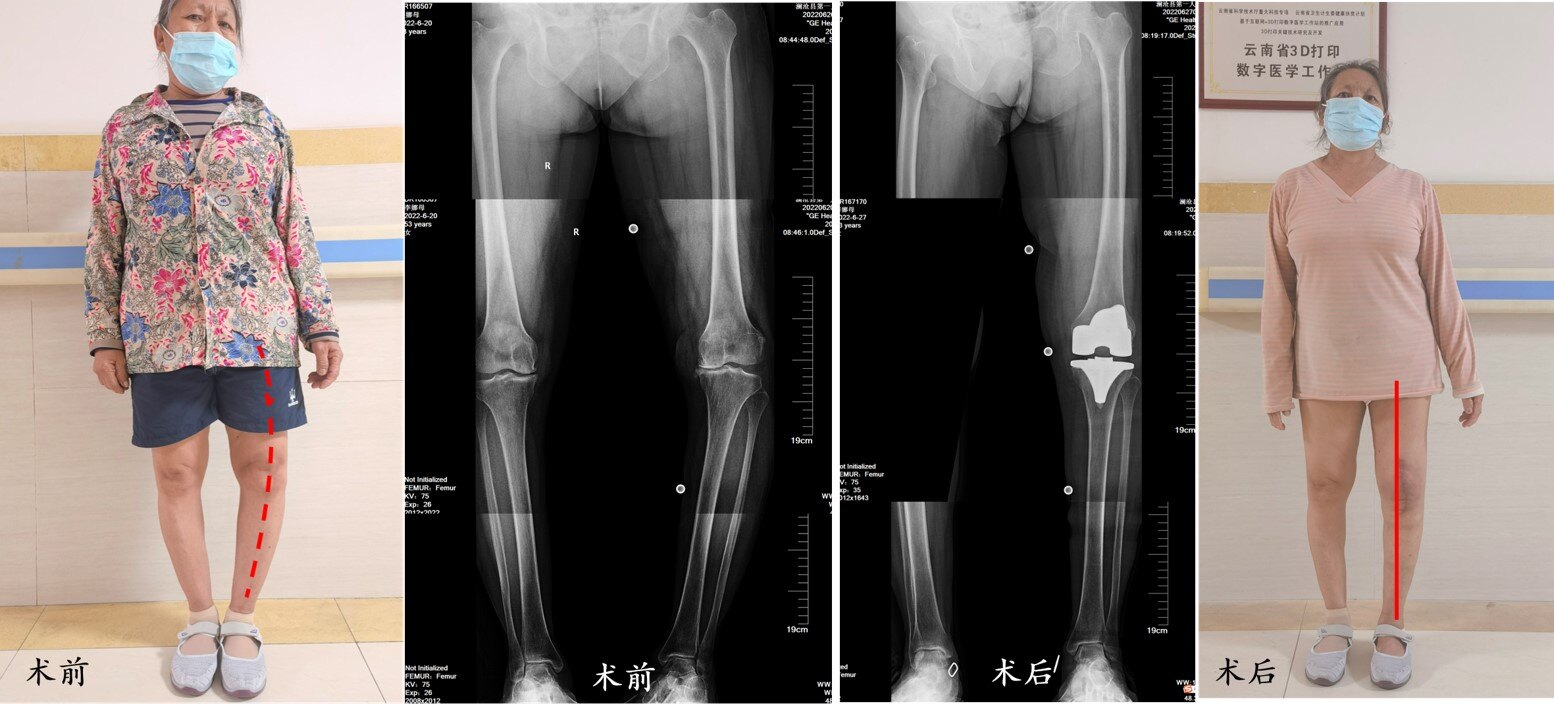

病例4(图7):61岁的李女士双膝关节反复肿痛7年多,平时的行走活动受到严重影响,甚至难以操持一些简单的家务,遂来到澜沧县第一人民医院骨科就诊,X线检查发现膝关节已经明显的磨损、变形,于是骨科团队的帮助下先选择了左侧人工膝关节置换手术,解除了关节病痛,下肢的内翻畸形也得到了矫正。手术后第1天就开始了下床活动进行恢复锻炼,第6天出院回家继续康复。

图7. 李女士因左膝严重骨关节炎接受了人工膝关节置换手术。

病例5(图8): 钟女士,66岁,右膝关节在10年前一次外伤后开始出现间断疼痛不适,膝关节疼痛症状逐渐加重,并出现了外翻变形,经过休息、理疗、药物等治疗方式没有明显效果,尤其是近3年来钟女士的日常生活受到明显影响。于是在澜沧县第一人民医院骨科选择了人工膝关节置换手术。手术以后顺利康复,膝关节疼痛缓解、外翻畸形得到矫正,目前已经可以外出散步、逛逛风景,享受老年生活。

图8. 钟女士因右膝骨关节炎接受了人工膝关节置换手术